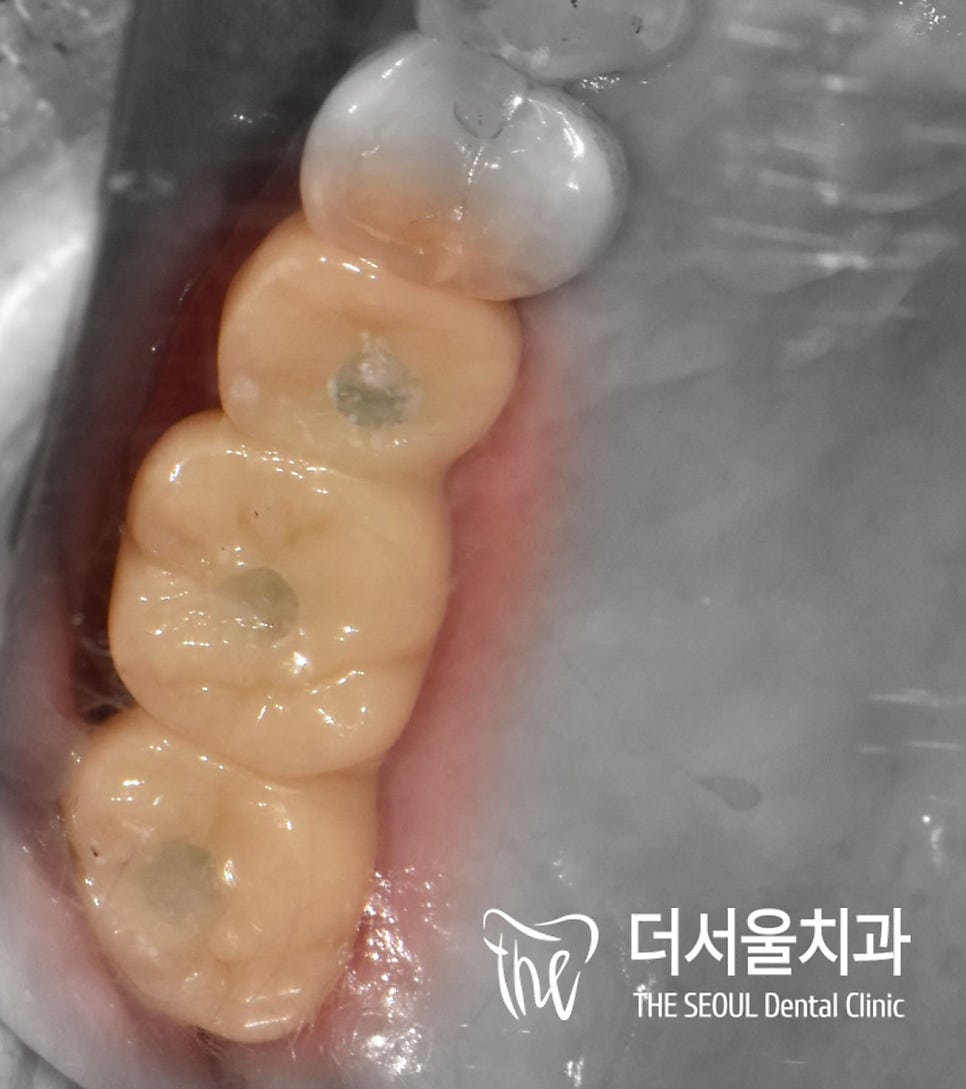

4. 최종 결과

상악 우측 어금니

모든 진료가 마무리된 모습입니다.

픽스처 간의 간격도 적절하고

위쪽에 지르코니아 브릿지를

올려드렸습니다.

수진동 임플란트 진행 시

컴퓨터 진단을 기반으로

더욱 안전하고 정확한 식립을

진행하였기에

장기적으로도 불편감 없이

오래오래 사용하실 수 있을 겁니다.